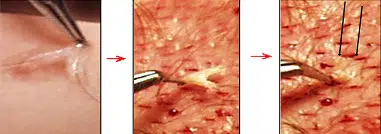

2. Make initial “marking incisions” along the anterior border of the transition zone. (Fig.-16B)

These “marking incisions” should be about 1 cm apart and slightly irregular. Placing some anterior to and some posterior to the drawn line begins the process of creating macro-irregularity. Making these “marking incisions” first ensure you will not lose the position of the hairline if your drawing is accidentally wiped off during procedure. They allow you work safely in other areas without fear of losing your initial design.

Fig 16B: STEPS IN CREATING THE HAIRLINE:(x ) “Marking incisions” along the anterior border of the transition zone (TZ). (y) “Marking \incisions” around the “fronto-temporal” angle using existing hairs as guides . (z) The incisions in the defined zone (DZ) are created before doing work in the transition zone